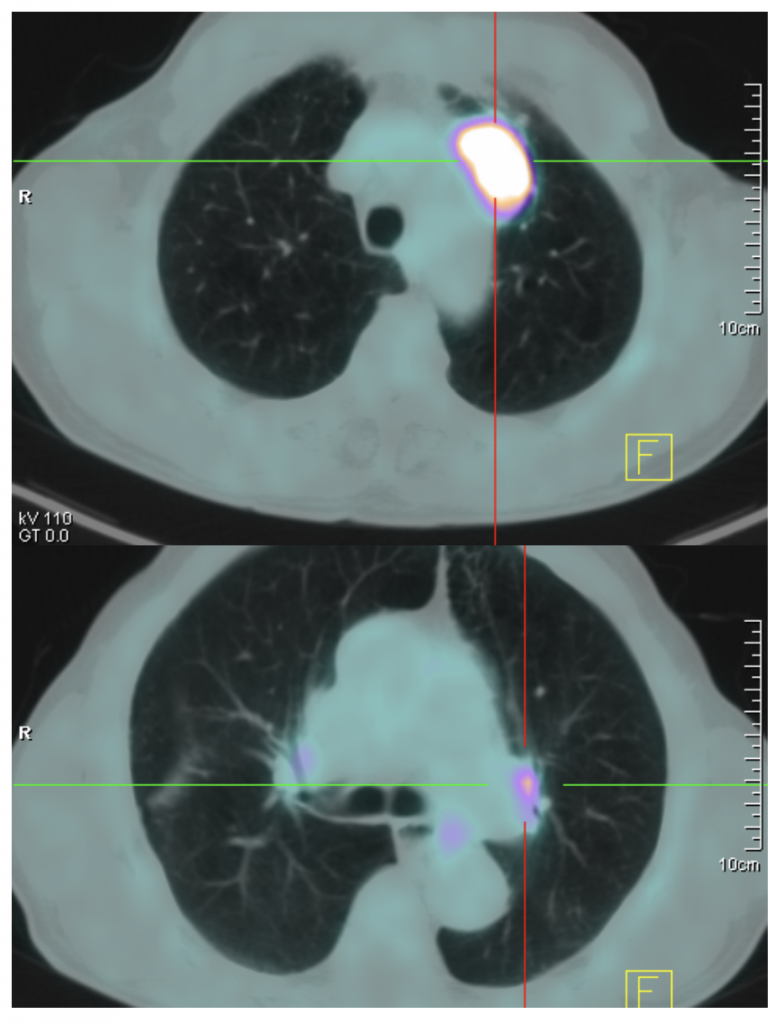

Se realiza PET-TAC para estadiaje porque en pacientes candidatos a tratamiento radical, esta indicada la realización de PET o PET-TAC para evaluar el mediastino y posibles metástasis extratorácicas.

PET-TAC es la abreviatura de tomografía por emisión de positrones-tomografía axial computarizada. Se trata de una técnica de medicina nuclear que nos permite obtener imágenes de la actividad metabólica de nuestras células gracias a un radiotrazador radiactivo que en este caso es la glucosa marcada con Flúor 18. La importancia de la técnica radica en que nos permite observar zonas con un consumo elevado de glucosa como son los tumores por ello nos permite valorar la presencia de metástasis de un tumor primario o evaluar la eficacia de un tratamiento quimioterápico o radioterápico.

En nuestro caso observamos una masa pulmonar hipercaptante que afecta al cayado aórtico en la primera imagen y en la segunda podemos ver hipercaptación en ambos hilos pulmonares que tienen una forma redondeada u ovalada por lo que se trata de adenopatías biliares afectadas por el tumor primario.